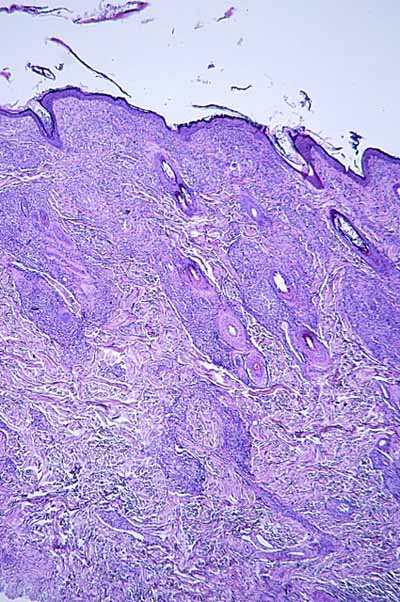

Photo 8 (Hémalun Eosine X 40) : L’épiderme est parsemé de vésiculo-pustules sous-cornées,

extensives, planes, dont le toit, composé de fines lamelles de kératine orthokératosique, est fragile.

Le derme montre un infiltrat de topographie péri-vasculaire.

Le patron lésionnel est celui d’une dermatite psutuleuse sous-cornée périvasculaire.

Légendes de la Photo 8 :

- Pointe de flèche turquoise : pustule intra-épidermique sous-cornée

- Flèche orange : infiltrat dermique de topographie péri-vasculaire

- Étoiles rouges pleines : vaisseaux sanguins

- Étoiles rouges vides : follicules pileux

Photo 9 (Hémalun Eosine X 40) : Les pustules sous-cornées qui parsèment l’épiderme,

peuvent ponter l’abouchement de plusieurs follicules pileux voisins.

Légendes de la Photo 9 :

- Double flèche noire : épiderme

- Double flèche pointillée noire : derme

- Pointes de flèche turquoise : délimitation de la pustule intra-épidermique sous-cornée qui ponte l’abouchement de trois unités folliculo-sébacées

- Pointes de flèche jaune : toit rompu de la pustule (fines lamelles de kératine orthokératosique)

- Cercles marrons : glandes sébacées

- Étoiles rouges pleines : vaisseaux sanguins

- Étoiles rouges vides : follicules pileux

- Étoiles turquoises : glandes sudorales apocrines épitrichiales

- Flèche orange : infiltrat dermique de topographie péri-vasculaire

- Dermatite d’interface lichénoïde granulomateuse (Photo 15)

- Dermatite périvasculaire superficielle et/ou profonde, pustuleuse, acantholytique ou non (Photo 19)

Photos 15 à 22 : Patrons lésionnels rencontrés dans les lésions histologiques de leishmaniose cutanée : Dermatite d’interface lichénoïde granulomateuse (15, HE X100), Dermatite d’interface lichénoïde et périannexielle granulomateuse (16, HE X100), Dermatite interstitielle granulomateuse nodulaire ou diffuse (Photo 17 HE X25) Péri-folliculite et adénite sébacée granulomateuses (18 HE X200), Dermatite périvasculaire superficielle et/ou profonde, pustuleuse, acantholytique ou non (19, HE X25) Vascularite (20, HE X400), Infiltrat inflammatoire riche en macrophages, plasmocytes et granulocytes éosinophiles (21 & 22, HE X1000).